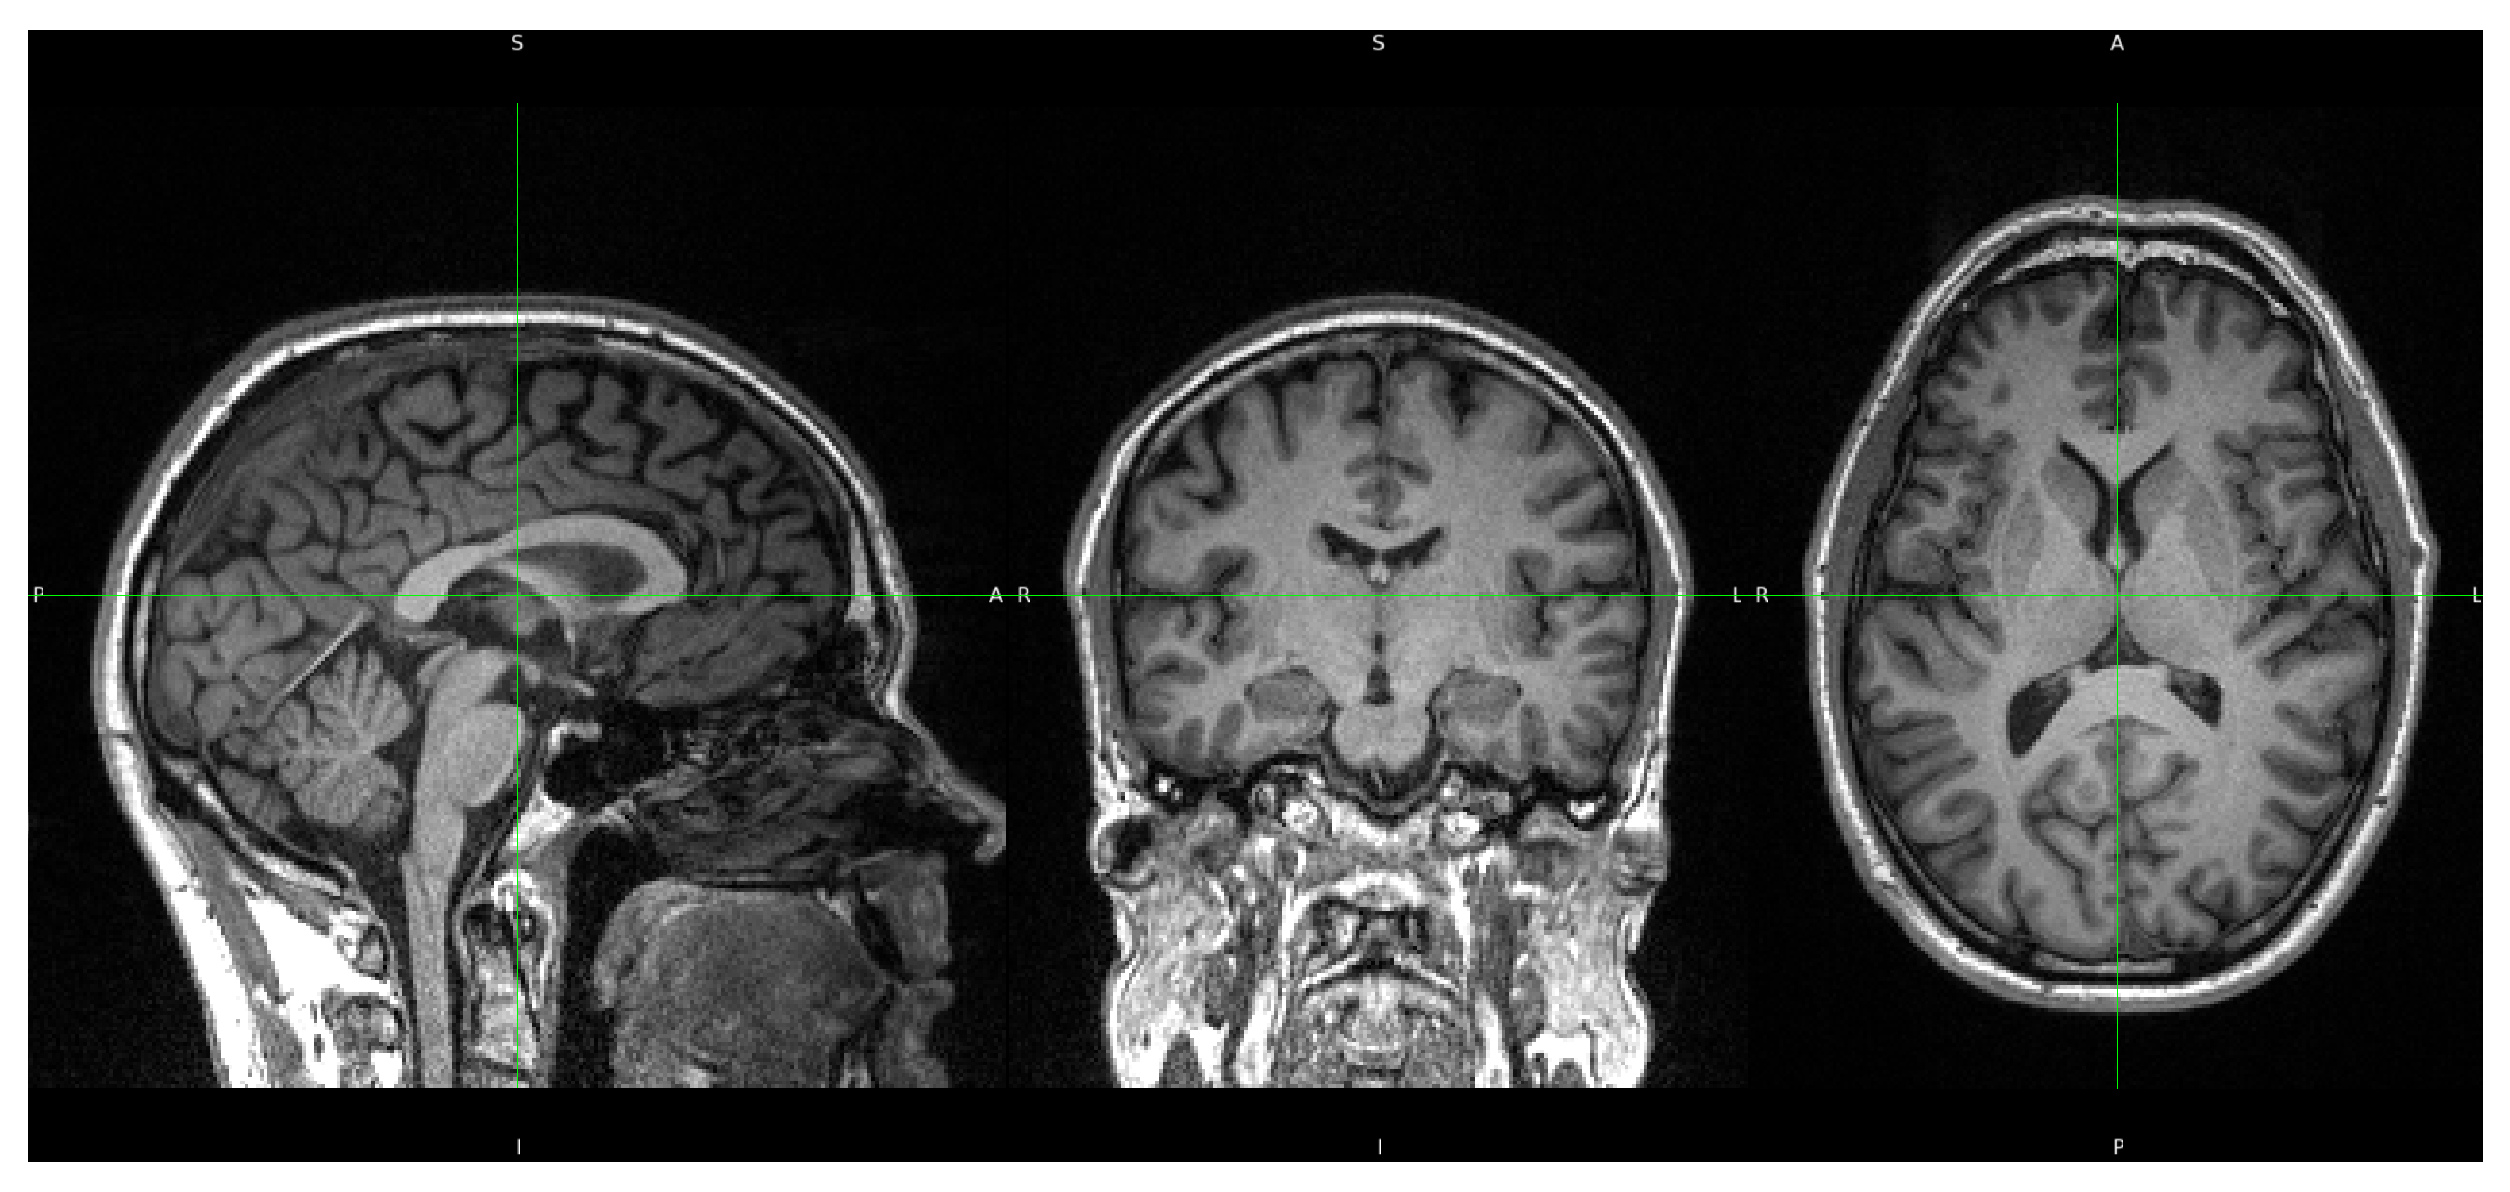

For the current morphometric analyses, we utilized only the high-resolution T1-weighted images, acquired using a 3D MPRAGE sequence. The acquisition parameters included a spatial resolution of 1.0 mm isotropic ( 1 × 1 × 1 mm3) across 192 sagittal slices, with a repetition time (TR) of 2500 ms, an echo time (TE) of 2.26 ms, and an inversion time (TI) of 900 ms. The field of view (FOV) was set to 256 × 256 mm2 with a corresponding matrix size of 256 × 256, and parallel imaging was employed using GRAPPA with an acceleration factor of 2.

Figure 1 shows a representative T1-weighted image from our dataset, demonstrating the high tissue contrast necessary for accurate morphometric analysis. The corresponding FreeSurfer-generated segmentation mask, which forms the basis for our morphometric measurements, is illustrated in Figure 2. These images exemplify the quality standards maintained throughout our dataset.